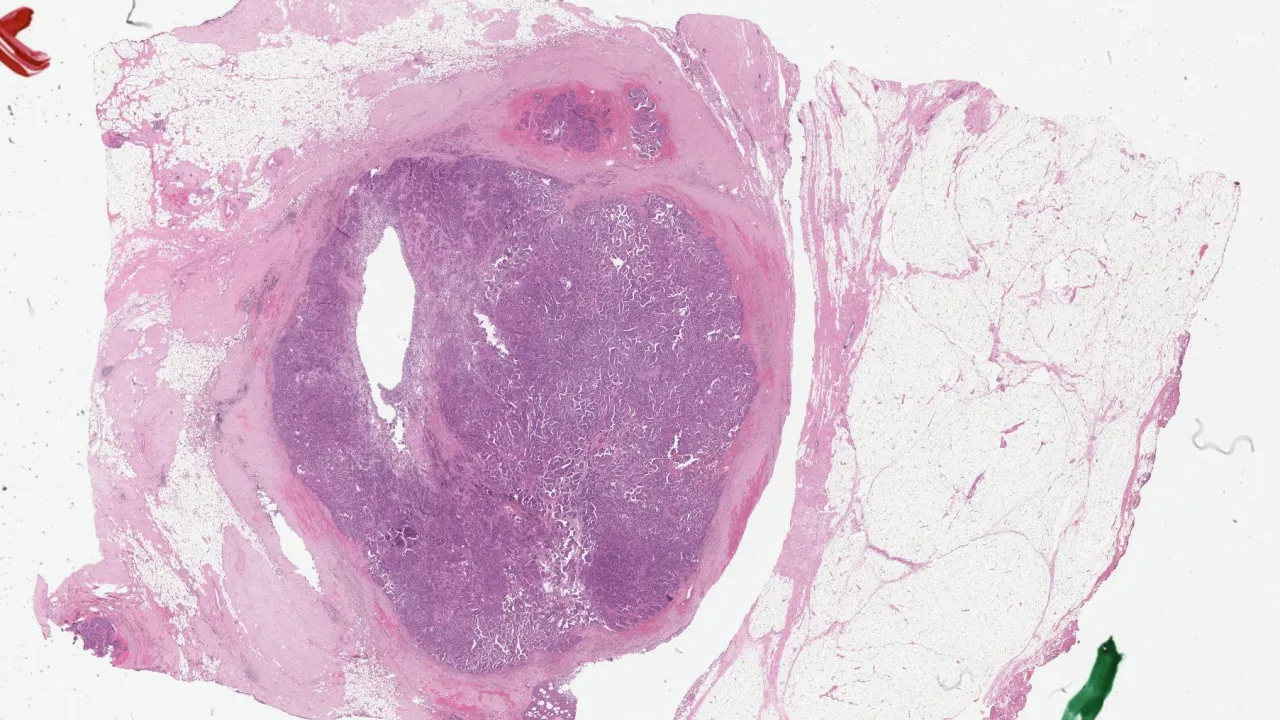

Lymph Nodes, Mixed phenotype acute leukemia, H&E stain